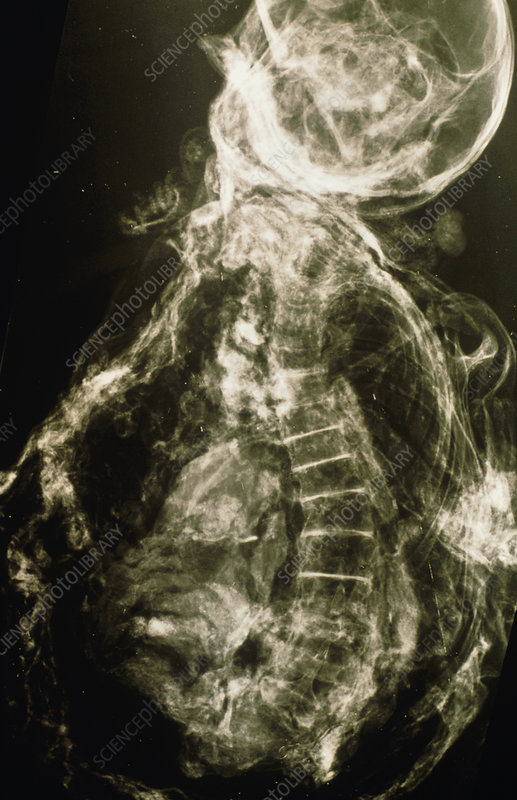

"Cô gái Yde" là một xác ướp 2.000 năm tuổi, được phát hiện trong đầm lầy Stijfveen, Hà Lan vào năm 1897. Nhiều người tin rằng cô gái trẻ này có thể đã bị hành quyết hoặc bị hiến tế.

Cô gái Yde được xác định khoảng 16 tuổi, chỉ cao hơn 1 mét, chết vào khoảng năm 54 trước Công nguyên đến năm 128 sau Công nguyên.

Khi xác ướp được phát hiện, cô gái có sợi dây thắt nút quấn quanh cổ và vết đâm gần xương đòn, cho thấy có thể cô đã bị giết hại.

Cô gái Yde có chứng vẹo cột sống làm suy nhược cơ thể, bàn chân phải sưng tấy dẫn đến đi khập khiễng.